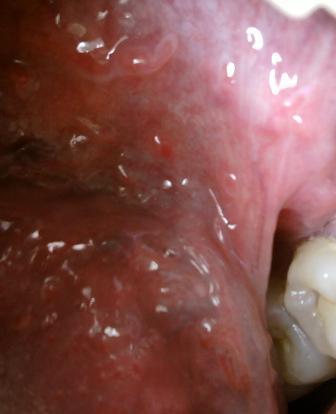

哪种方法治疗尖锐湿疣是比较安全的要想更好的治疗疾病,就应该在主治医师的指导之下,根据自身病情来制定适合的治疗方法,专病专治,才能够在治疗的道路上少走弯路。尖锐湿疣给人体健康带来的危害是比较大的,所以患病之后及时去医院治疗是很关键的。